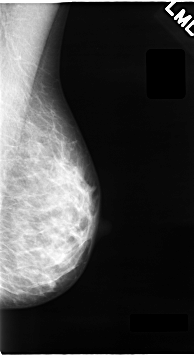

C_0063_1.LEFT_MLO

LEFT_MLO LINES 4648 PIXELS_PER_LINE 2512 BITS_PER_PIXEL 12 RESOLUTION 50 NON_OVERLAY